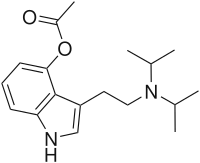

| 4-Acetoxy-DiPT | artificial | 4-OCOCH3 | CH(CH3)2 | CH(CH3)2 | 4-acetoxy-N,N-diisopropyltryptamine | 936015-60-0 |